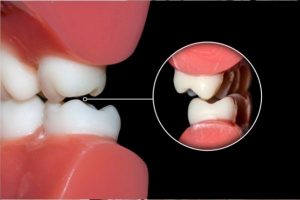

¿Qué es el bruxismo y cómo se combate?

Puede que el término bruxismo te suene algo extraño, pero es una enfermedad que padecen muchas personas, e incluso tú podrías tenerla y ni si quiera lo sepas. Te hablamos sobre esta enfermedad para que la conozcas a profundidad.